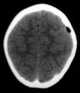

Depressed skull fracture

A skull fracture is a break in one or more of the eight bones that form the cranial portion of the skull, usually occurring as a result of blunt force trauma. If the force of the impact is excessive, the bone may fracture at or near the site of the impact and cause damage to the underlying structures within the skull such as the membranes, blood vessels, and brain. [Source: Wikipedia ]